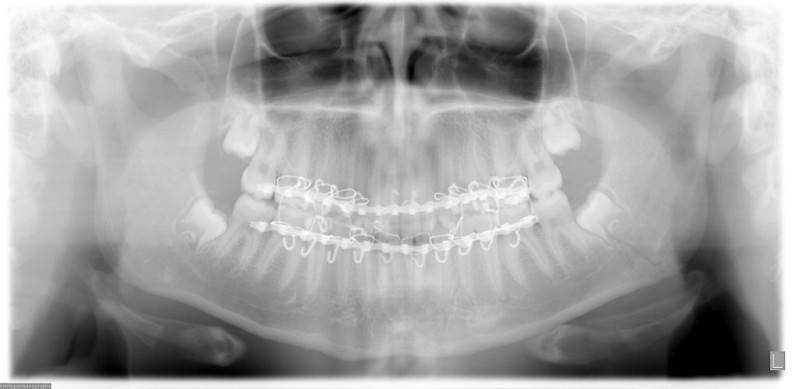

Facial Fracture X-Rays